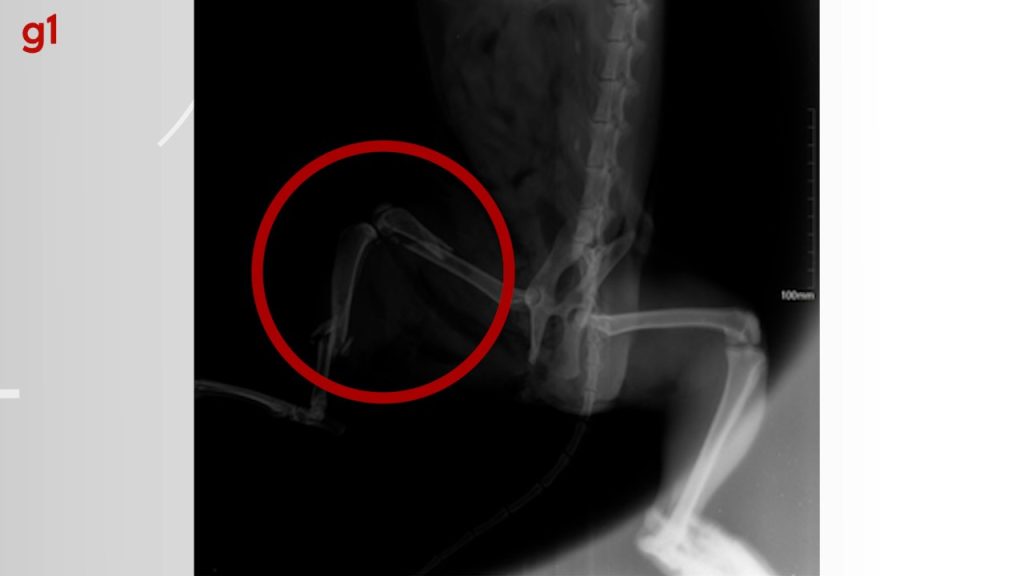

Raio-x mostra fraturas do gato após levar um tiro na perna

O gatinho Romeu morreu neste domingo (10), horas depois de passar por duas cirurgias. O felino teve a pata quebrada em dois lugares após ser atingido por um tiro que atravessou o membro. O caso aconteceu em Paraíso do Tocantins.

O gato, de três anos de idade, ficou em observação após passar pelas cirurgias e colocar placa em um dos ossos. Por conta dos machucados internos, Alessandra foi informada que as próximas 24 horas da recuperação de Romeu seriam decisivas.